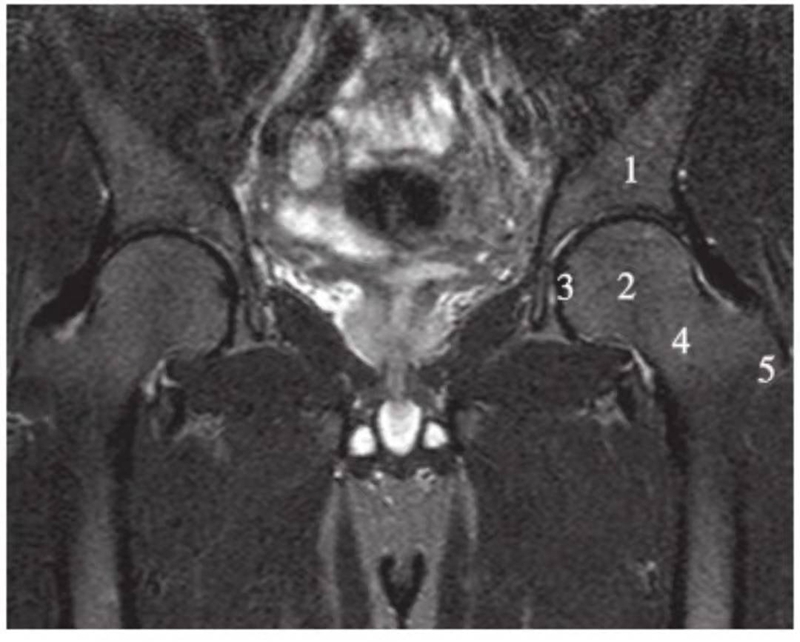

正常髋关节经股骨头前缘层面T1WI像

1.股骨头;2.耻骨;3.髂骨;4.髂腰肌;5.内收肌群;6.臀小肌;7.臀中肌;8.关节囊及髂股韧带